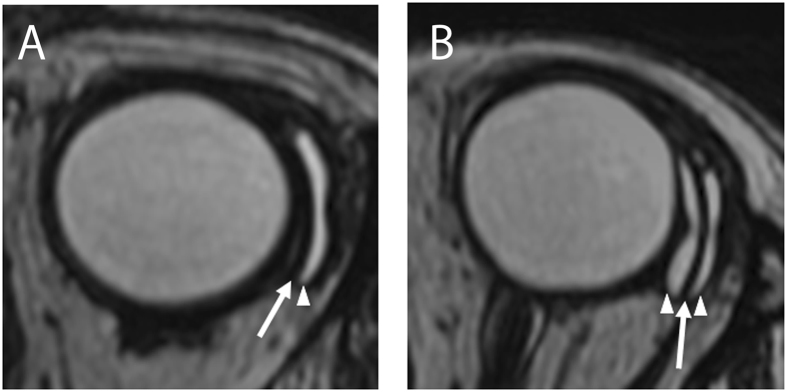

In all cases, a curvilinear low-intensity band that corresponded to the signal intensity of the silicone material was observed at the location of the endplate. Areas with the same high intensity as the intraocular fluid, corresponding to the signal intensity of the aqueous humor in the filtering bleb, were located adjacent to the endplate. In 28 out of 52 eyes (53.8%), the signal corresponding to the aqueous humor in the filtering bleb was detected on the outside of the endplate. The remainder of the eyes (46.2%) showed aqueous humor signals on both sides of the endplate. Based on this information, we classified the eyes into two groups: the single bleb layer group and the double bleb layer group (Fig. 1). Three-dimensional images were obtained in all cases. In both the single and double bleb layer groups, four signal-free holes were detected in each bleb layer. Because the endplate has four fenestrations, each signal-free hole was located on both sides of these fenestrations in the endplate (Fig. 2; Supplement Movie 1S).

Figure 1.

Magnetic resonance imaging scans of eyes with the Baerveldt glaucoma implant. (A) A case with a single bleb layer. (B) A case with a double bleb layer. A curvilinear low-intensity area was observed at the location of the endplate (arrows). A high-intensity area corresponding to the signal intensity of the aqueous humor, was located adjacent to the endplate (arrowheads).